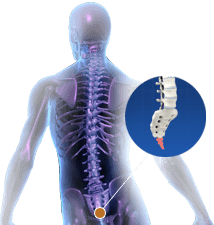

Coccygectomy

Coccygectomy is a surgical procedure which involves removal of part or entire portion